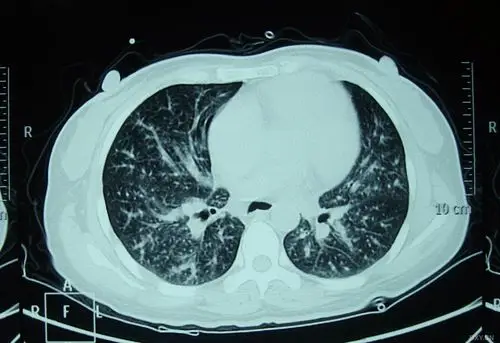

【影像读片】体检发现,左下肺结节影.

【影像读片】双肺多发结节,团块,空洞

【影像读片】影像读片 肺泡细胞癌?结节病?抑或其它 [病例帖]

双肺多发结节灶,部分环型

肺结节读片(7):空泡的意义